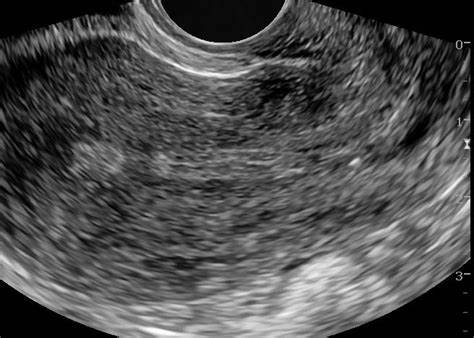

宫腔粘连可以做试管婴儿吗?